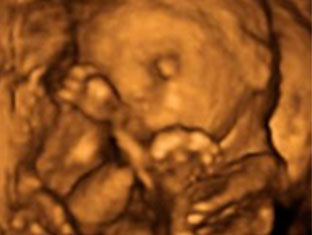

En la ecografía de la semana 18 se visualizan las cuatro cámaras cardiacas y mediante una ecografía Doppler se puede ver el recorrido de todos los vasos sanguíneos del cuerpo del bebé. Podemos ver también cómo se chupa el dedo, cómo bosteza e incluso cómo sonríe.